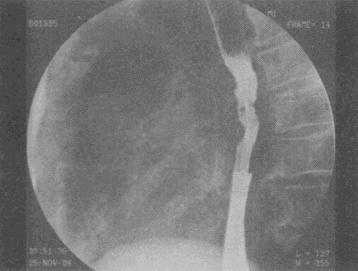

2.男,74歲,進行性吞咽困難半年,結合圖像,最可能的診斷為

正確答案:D解題思路:食管中段鋇劑通過見半圓形充盈缺損,病灶附近黏膜粗細不均、扭曲,結合患者病史,考慮食管中段癌性病變。